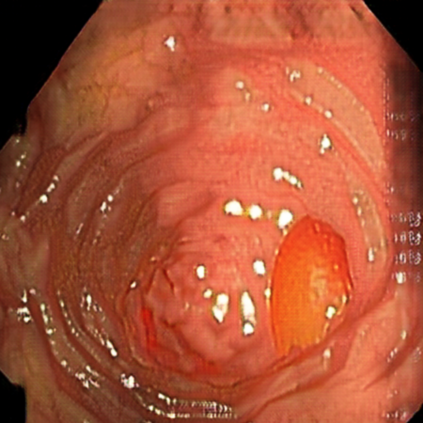

Deep learning has shown excellent performance in analysing medical images. However, datasets are difficult to obtain due privacy issues, standardization problems, and lack of annotations. We address these problems by producing realistic synthetic images using a combination of 3D technologies and generative adversarial networks. We use zero annotations from medical professionals in our pipeline. Our fully unsupervised method achieves promising results on five real polyp segmentation datasets. As a part of this study we release Synth-Colon, an entirely synthetic dataset that includes 20000 realistic colon images and additional details about depth and 3D geometry: https://enric1994.github.io/synth-colon